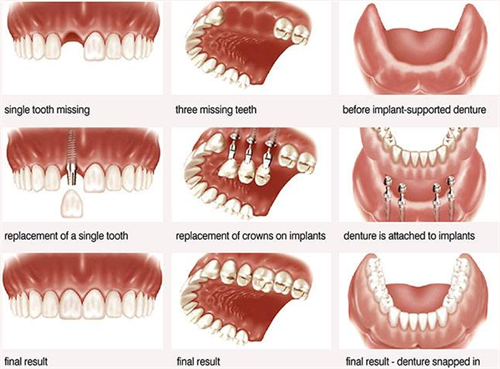

他们致力于为患者提供多方位的口腔健康解决方案,包括牙齿矫正、牙周治疗、口腔种植等。